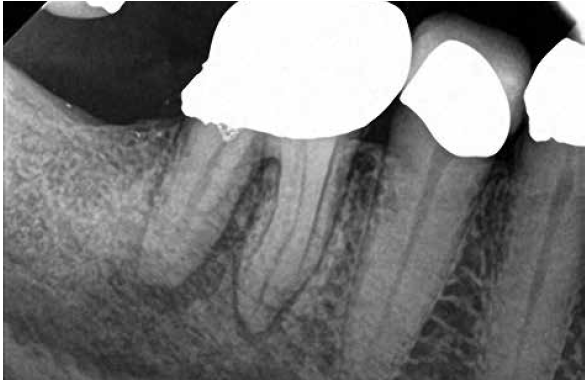

A body of research has emerged in recent years on the management of severe dental pain, exemplified by the diagnosis of an acute apical abscess where drainage cannot be achieved, symptomatic apical periodontitis, or irreversible pulpitis.11 An example of an acute apical abscess is depicted in Figure 1 and Figure 2. These conditions typically represent the most severe discomfort experienced by patients, and consequently, they serve as an excellent model for pain management. Treatment strategies for these issues and other painful conditions should include both definitive treatments for the diagnosed condition as well as adjunctive pharmacologic management.

(1.) A 74-year-old male presented with an acute apical abscess associated with tooth No. 30. The pre-operative periapical x-ray revealed evidence of apical pathology.

Figure 1

(2.) The infection was managed with oral antibiotics, root canal therapy, and a combination of ibuprofen and acetaminophen to manage the preoperative and postoperative discomfort.

Figure 2